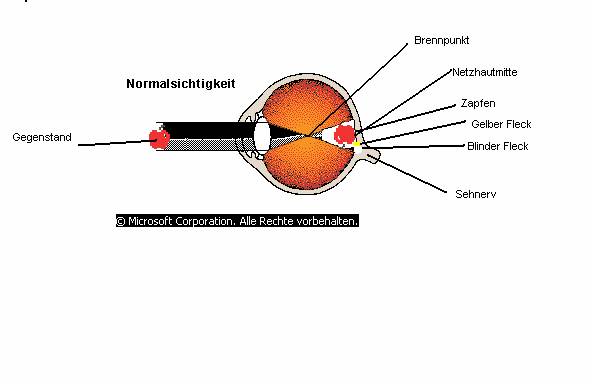

Die zentrale Sehschärfe wird im Medizinischen auch als „Visus“ bezeichnet. Der Visus ist die Fähigkeit des Auges, zwei nah beieinander liegende Punkte getrennt voneinander wahrzunehmen. Der Ort, an dem die Sehschärfe bestimmt wird, ist die Netzhautmitte, wo im Punkt des schärfsten Sehens (Fovea centralis oder auch Gelber Fleck) die Zäpfchen für die Sehschärfe zuständig sind.

Aus physikalischer Sicht wird ein Gegenstand für uns sichtbar, wenn das von einer Lichtquelle (z.B. Sonne, Lampe) ausgestrahlte Licht von diesem Gegenstand reflektiert wird. Diese reflektierten Lichtstrahlen werden in der Linse des Auges gebündelt, sodass auf der Netzhautmitte ein scharfes Bild entsteht. Das entstandene Bild steht auf dem Kopf. Die Lichtstrahlen treffen auf die Zapfen der Netzhaut. Die Informationen, die bei jedem Zapfen entstehen, so genannte elektrische Nervenimpulse, werden im gelben Fleck gesammelt und über den blinden Fleck an das Gehirn weitergeleitet. Dort entsteht das richtige Bild. (Abb1)

Auf der Bild 1 sieht man den Querschnitt eines Auges, das gerade einen Gegenstand fokussiert.

Abb1: Der Apfel reflektierten

Lichtstrahlen, die in der Linse des Auges gebündelt werden, sodass auf der

Netzhautmitte ein scharfes Bild entsteht. Das entstandene Bild steht auf

dem Kopf. Die Lichtstrahlen treffen auf die Zapfen der Netzhaut. Die

Informationen, die bei jedem Zapfen entstehen, die so genannte elektrische

Nervenimpulse, werden im gelben Fleck gesammelt und über den blinden Fleck

an das Gehirn weitergeleitet. Dort entsteht das richtige Bild.

Bild 1: Titel des Bildes, aus: Microsoft Corporation 2000, Suchbegriff: Auge.